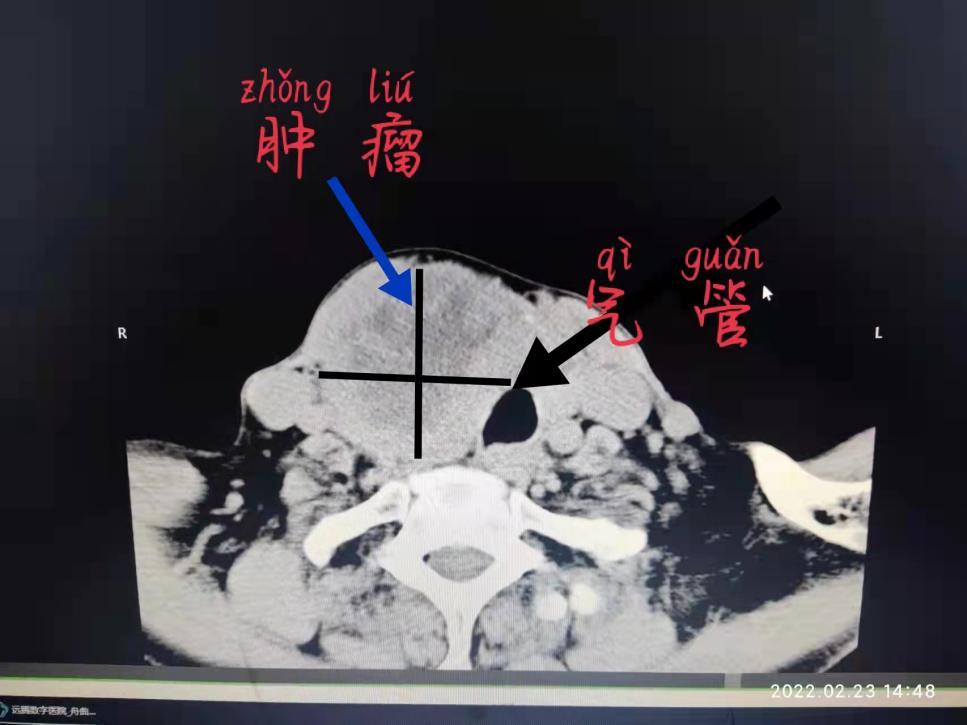

据了解,该患者为67岁老年女性,因“右颈前肿物10年余,进行性增大3年”以“甲状腺肿瘤”收住入院。患者入院前10余年无明显诱因右颈前出现一肿块,患者自觉无明显不适情况,未予以重视及就诊治疗。近日,患者吞咽困难、呼吸困难情况逐渐加重,手术意愿强烈,至入院前,患者颈前肿块增大,患者为进一步诊治,入院门诊就诊并经会诊后,遂收住入院。

何为胸骨后甲状腺肿?是指颈部肿大的甲状腺因自身重力作用和胸腔内负压的吸引,逐步下坠扩展,进入胸廓入口,使肿大甲状腺部分或完全坠入胸骨后间隙,故又可称为坠入性胸腔内甲状腺肿,可造成患者胸闷、气短、呼吸困难(尤以夜间平躺时明显)、吞咽困难、声音嘶哑、颈静脉怒张,纵膈内结构复杂,且胸骨后甲状腺肿周围多为较大的血管,一旦损伤,后果严重。